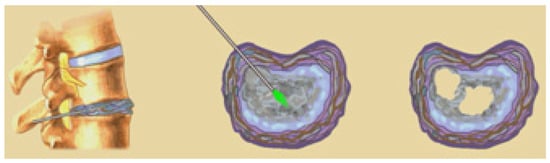

4.1. LRD Puncture

4.2. LRD after Surgical Interventions on the Spine as a Means of Preventing the Development of Recurrent Disc Herniation, Instability of the Affected Segment and Further Development of the DDD